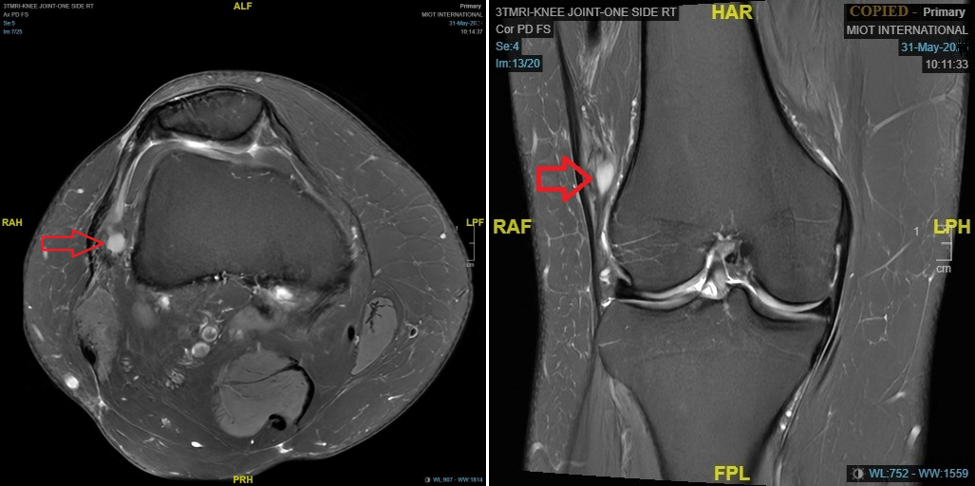

During the clinical examination, a point tenderness was appreciated over the lateral femoral condyle with no effusion or synovitis. Range of motion was 0–100° further restricted and associated with pain. The Lachman test indicated no laxity. Collateral ligaments were stable, and no distal neurovascular deficits. MRI images (Fig. 1) reported by the senior musculoskeletal radiologist suggested a probability of nodular synovitis/ganglion cyst/venous malformation as potential diagnoses, as the lesion is <5 cm with no distinct features suggesting toward the SS, it is not included in the differentials. The lesion demonstrated well-defined margins, homogenous signal, lack of aggressive bone or soft-tissue invasion, and no red flags, including periosteal reaction or bone destruction so contrast MRI was not done. Surgery was conducted under general anesthesia and adductor canal block with tourniquet control. Standard anterolateral, anteromedial portals, superolateral, and accessory anterolateral portals were established. During the arthroscopic evaluation, anterior cruciate ligament and posterior cruciate ligament appeared intact and the medial and lateral compartments appeared pristine, except for the lateral gutter showing a cystic swelling adhered to the lateral femoral condyle, we thought of venous malformation/ganglion cyst (Fig. 2 and 3) for which biopsy was obtained and sent for histopathological examination, rest of the lesion removed by using motorized shaver and surrounding tissue was cauterized to ensure lesion free margins and knee portals were closed and regular physiotherapy initiated postoperatively.

SS is known to have a benign presentation often diagnosed after surgical excision of misdiagnosed benign lesions, same happened with our case as well, but with suspicion of lesion we have employed complete resection of lesion through arthroscopy and thermal ablation of the margins for tumor-free margins as it is one of the employed technique in the reviewed literature. As the MRI characteristics of intra-articular SS are generally non-specific, as the lesion is <5 cm, demonstrating homogenous signal intensity with well-circumscribed margins, making accurate diagnosis more difficult [15], which made our diagnosis doubtful. Till to date, only nine cases of intra-articular SS have been reported with specific MRI findings [16]. Intra-articular SS is a highly uncommon condition. The knee joint is the most frequently affected site, accounting for 88% of cases. Due to its uncommon occurrence, slow growth and vague clinical and radiological features, intra-articular SS can cause a significant delay in diagnosis and treatment [6]. Biphasic SS demonstrated a markedly higher survival rate in histological comparisons to monophasic variants, indicating distinct biological behaviors associated with the different histotypes [10,17]. This case report is interesting in the sense that we could have been easily misled to not address the nodular lesion, as the patient was not significantly symptomatic except for terminal flexion restriction. Despite the higher threshold to explore the lesion, a correct decision was made ultimately which guided us to the reality of the presence of a SS. The fact that the patient had symptoms for 4 years before the first “evidence” of the cyst creates the possibility of this lesion being undercover for several years which was excised through arthroscopy and followed by chemo and radiotherapy. Excision of these masses has shown to leave residual tumor in up to 82% of cases [15,18,19]. (Table 1). Radiotherapy has a well-established role in improving local control, but while surgery and radiation therapy have achieved excellent local control, distant metastasis remains the principal problem limiting survival [20,21]. Adjuvant chemotherapy helped to increase long-term survival for SS, a soft-tissue sarcoma that is susceptible to chemotherapy [9]. Ifosfamide-based chemotherapy has been associated with an improved survival in patients with SS [22]. Chemotherapy combined with surgical excision and radiation therapy increases overall survival to 80–95% after 3 years [23,24]. This was employed in our case showing no recurrence after 12 months with follow-up PET CT and MRI. Nevertheless, it is important to include intra-articular SS in the differential diagnosis of an intra-articular mass, particularly in the knee joint, when the radiological features do not align with those of SOC, synovial hemangioma, or PVNS.